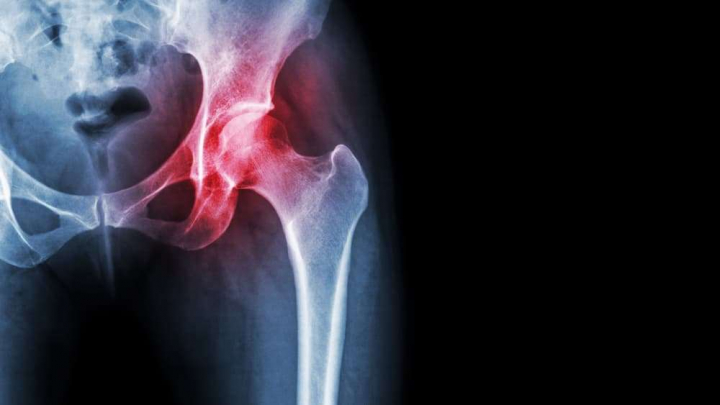

This meta-analysis from randomized controlled trials (RCTs) investigated the efficacy of Kinesio Taping in reducing pain and improving knee function in patients with knee osteoarthritis (OA).